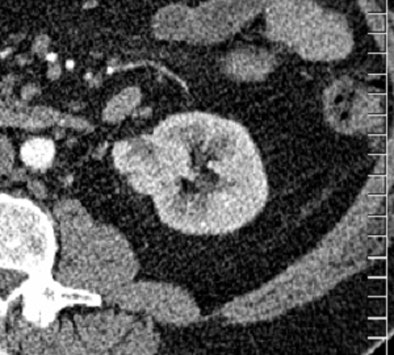

| Above, 3.5-cm left renal mass incidentally found at CTC of a 64-year-old man; further evaluation was recommended. Follow-up CT with and without contrast (below) demonstrated an enhancing mass. Patient underwent nephrectomy, and pathology was stage I renal cell carcinoma. The patient is still alive and without metastases, 4.5 years later. Images courtesy of Stacy O'Connor, MD. |